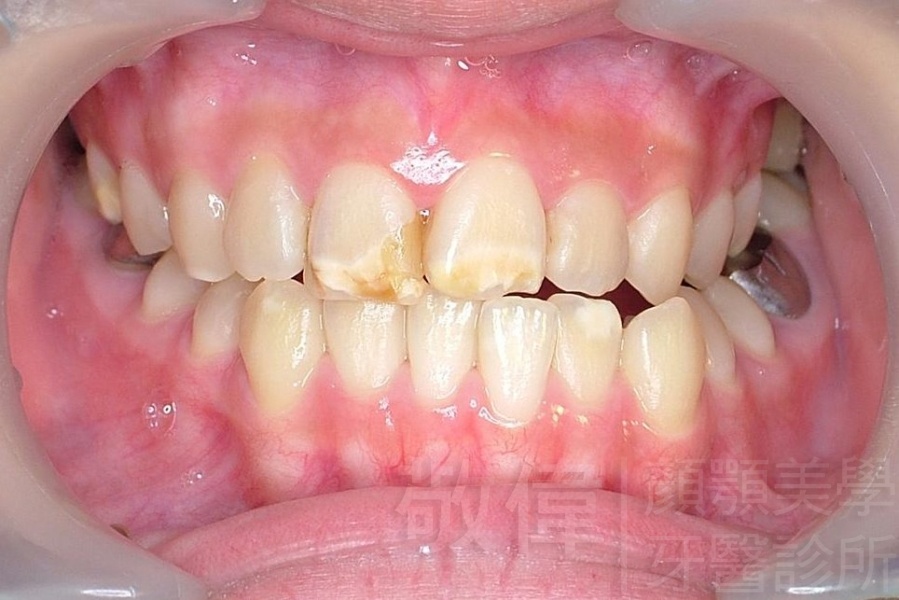

齒顏矯正/戽斗、亂牙、爛牙,變身 免植牙的健牙美女

<個案說明>

變臉矯正,原來戽斗妹跟大歪臉變成自信正妹

經由本院3D數影X光影像儀分析、與3D齒顎顏矯正技術,再配合口腔顎面正顎專科醫師施以正顎手術治療,雙方共同合作,使患者臉部外觀有很好的改善,大歪變小歪,產生了天南地北的大改變,她的人生也整個變得不一樣。

因為矯正與正顎手術的配合,使「戽斗妹」變成了「陽光正妹」,完全的改變了她的人生,在面對各種場合、與人交際都散發出自信微笑。所以,奉勸家長,如果小朋友有臉顎畸型的問題,應該考慮配合做這種簡單、安全、有效的正顎手術。